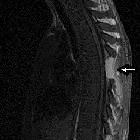

A rare cause

of acute paraplegia: granulocytic sarcoma. Sagittal spinal cord MRI T1: complete regression of compression process (the epidural mass was completely resected) with stigmata of laminectomy D6 (arrow)